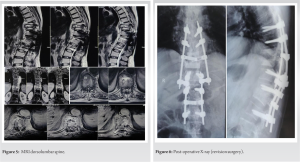

This case involves a 63-year-old gentleman who complained of backache along with fever and loss of appetite 2 years back which lasted around 4–5 months. The patient took over-the-counter medications for the above complaints during the initial period of 4–5 months. As the symptoms were not relieved, the patient got MRI done at the consult of an Orthopaedic surgeon, and a diagnosis of tubercular spondylitis involving D-12 and L-1 vertebral bodies and intervening disc along with pre- and para-vertebral collection was made (Fig. 1).

The patient was started on anti-tubercular therapy based on the clinicoradiological diagnosis of TB spine. Even after 6 months of anti-tubercular chemotherapy, the patient developed gradual onset weakness in bilateral lower limbs and was referred to our center. Due to the failure of chemotherapy as evidenced by progressive lower limb weakness even after 6 months of medical management, the patient was planned for surgery. Posterior decompression and pedicle screw fixation was done (Fig. 2). Pedicle screws were put in D11, D12, and L2 vertebrae. Post-operative course was uneventful and he was discharged with the continuation of anti-tubercular therapy. The patient was put on ATT regimen which consisted of HRZE (tablet isoniazid+tablet rifampicin+tablet pyrazinamide+tablet ethambutol) for initial 2 months followed by HRE for 7 months and then H+R for 9 months. At a 3-week follow-up visit, suture removal was done and the patient was mobilized using a walker. Till 15-month post-surgery, the patient was able to mobilize himself with the assistance of a cane or walker. He continued taking rifampicin and isoniazid combination drug during this period as per protocol. After 15 months of symptom-free period, the patient again presented to our OPD with complaints of fever and weakness in bilateral lower limbs and unable to walk for the past 10 days. On examination, the patient had spastic paralysis in extension in bilateral lower limbs, and UMN signs such as ankle clonus, patellar clonus, and Babinski sign were positive in both lower limbs. Deep tendon reflexes in bilateral lower limbs were exaggerated. The sensory loss was seen below the D10 level. The patient was catheterized due to urinary retention. Routine blood investigations, ESR, and CRP were found to be within normal limits. Radiological investigations were done (Fig. 3, 4, 5).

Based on the clinicoradiological findings, the patient was diagnosed with D9-D10 tubercular spondylitis with cord compression and neural deficits. Revision surgery was planned and the patient was prepared accordingly. Posterior decompression was done at D9-D10 level and pedicle screws were put in D7 and D8 level and the connecting rods interconnected to the previous rods at a lower level (Fig. 6). Post-operative stay was uneventful and the patient was discharged on post-operative day 4.